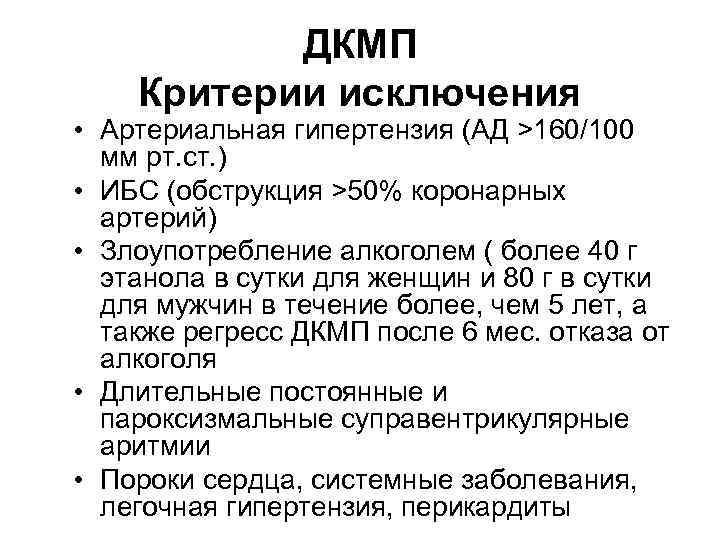

ДКМП Критерии исключения • Артериальная гипертензия (АД >160/100 мм рт. ст. ) • ИБС (обструкция >50% коронарных артерий) • Злоупотребление алкоголем ( более 40 г этанола в сутки для женщин и 80 г в сутки для мужчин в течение более, чем 5 лет, а также регресс ДКМП после 6 мес. отказа от алкоголя • Длительные постоянные и пароксизмальные суправентрикулярные аритмии • Пороки сердца, системные заболевания, легочная гипертензия, перикардиты

ДКМП Критерии исключения • Артериальная гипертензия (АД >160/100 мм рт. ст. ) • ИБС (обструкция >50% коронарных артерий) • Злоупотребление алкоголем ( более 40 г этанола в сутки для женщин и 80 г в сутки для мужчин в течение более, чем 5 лет, а также регресс ДКМП после 6 мес. отказа от алкоголя • Длительные постоянные и пароксизмальные суправентрикулярные аритмии • Пороки сердца, системные заболевания, легочная гипертензия, перикардиты